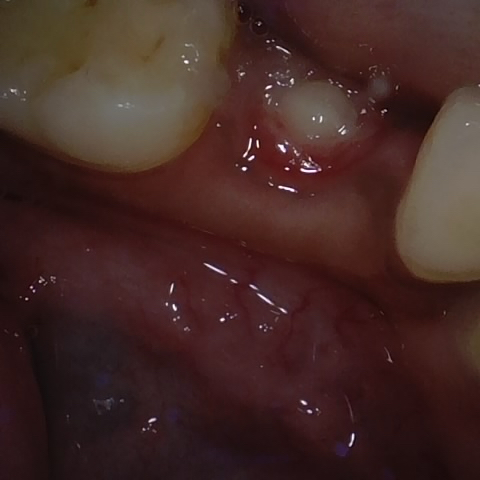

Annotated as "Good"